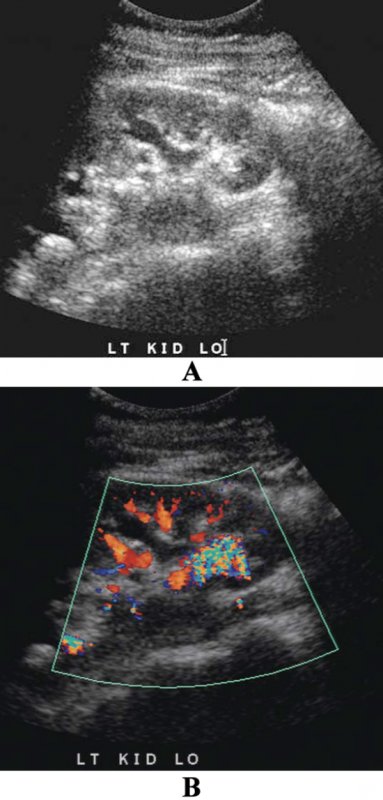

Артефакт ложного потока по сути является потоком реально жидкости, но не крови, например, амниотическая или асцитическая жидкость. В качестве примера ложного потока также можно привести струю в мочевом пузыре. Таким образом, используемый в повседневной практике термин «ложный поток» по сути является неправильным, поскольку более корректно применять термин «некровянной поток» (фото 3, 4, 5).

Фото 3. УЗИ мочевого пузыря: струя мочи в мочевом пузыре. Поперечная проекция основания мочевого пузыря демонстрирует нормальный выброс жидкости из правого мочеточника